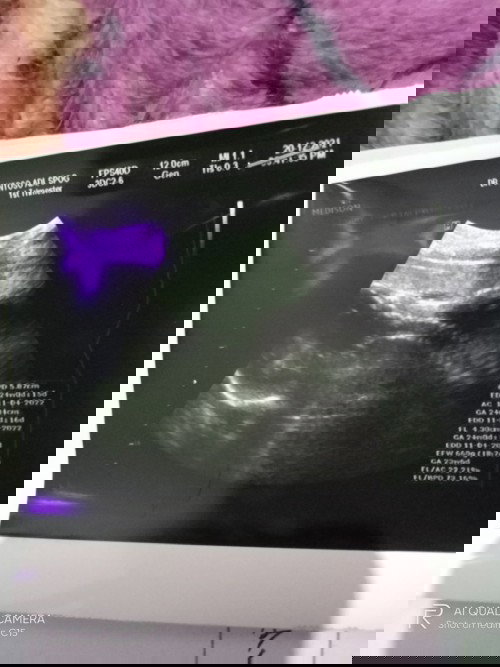

Bayi sungsang dan terlilit tali pusar

aku hamil anak pertama usia kandungan 24 minggu.. waktu usg ternyata baby ku posisinya sungsang dan terlilit tali pusar.. apa posisinya bisa berubah + lilitannya bisa lepas ya bun? Biar bisa lahiran normal, Takut banget soalnya..